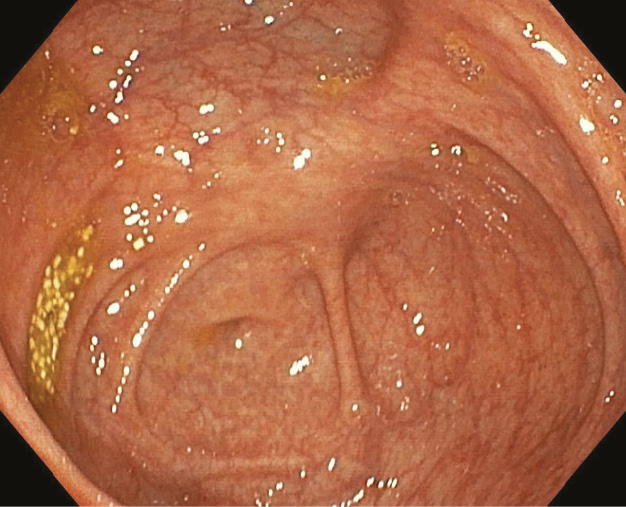

Рис. 5. Неизмененная слизистая оболочка толстой кишки с усилением сосудистого рисунка у больного с интенсивной диареей, лихорадкой и повышением С-реактивного белка после перенесенной инфекции SARS-CoV-2

Рис. 6. Минимальные воспалительные изменения слизистой оболочки толстой кишки (очаговая гиперемия, усиленный сосудистый рисунок, единичные мелкие геморрагии) у больного с диареей и лихорадкой после перенесенной инфекции SARS-CoV-2

6. Fig. 5. Unchanged colonic mucosa with enhanced vascular structures in a patient with severe diarrhea, fever and increased C-reactive protein after the SARS-CoV-2 infection

7. Fig. 6. Minimal inflammatory abnormalities in the colonic mucosa (focal hyperemia, enhanced vasculature, single small hemorrhages) in a patient with diarrhea and fever after the SARS-CoV-2 infection